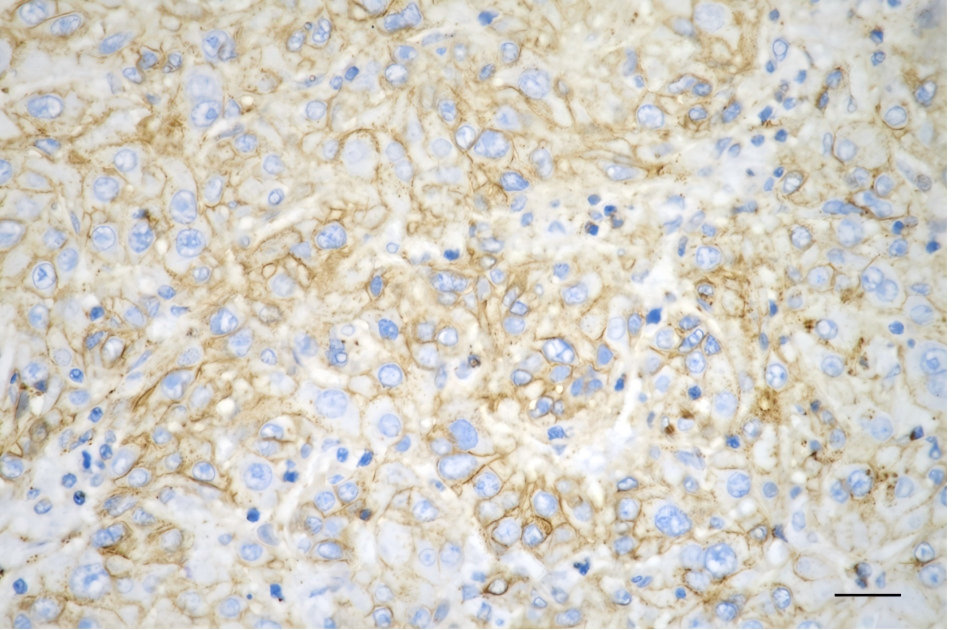

• Immunohistochemistry was performed on paraffin-embedded human hepatocarcinoma using flotillin 1 antibody. Antigen retrieval was done in sodium citrate buffer (pH 6.0). DAB was used for detection, with hematoxylin counterstaining. Images were acquired using a Nikon Ci-L Plus microscope (40× objective). Scale bar: 25 μm.